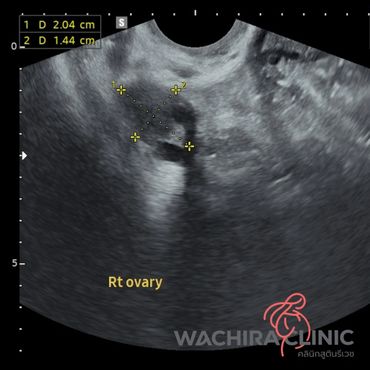

การอัลตราซาวด์มดลูกรังไข่ สามารถบอกความผิดปกติภายในมดลูกและรังไข่ได้ โดยแพทย์จะทำการอัลตราซาวด์ผ่านทางช่องคลอด ซึ่งจะสามารถมองเห็นมดลูกและรังไข่ได้ชัดเจนกว่าการอัลตราซาวด์ผ่านทางหน้าท้อง